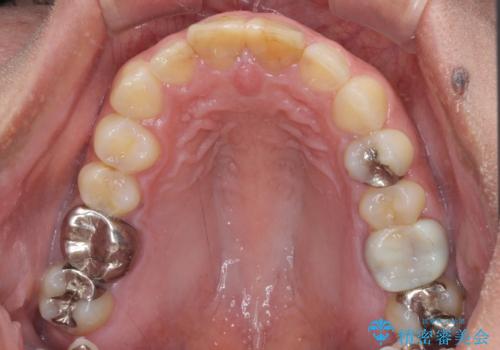

- 前歯の形と色を気にして来院された患者様です。

虫歯で神経を取り除いたことによる変色や充填物の着色などが認められたため、オールセラミッククラウンにて補綴することとしました。

また、咬耗により周囲の歯がすり減ったことで、前歯2本のみが長く見えていたため、周囲に長さを合わせることとしました。